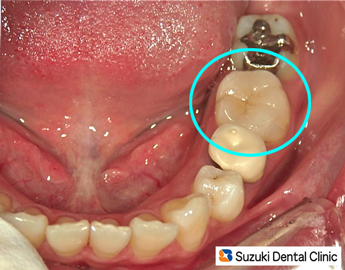

100%セラミック詰め物

コラム「100%セラミック詰め物」の画像